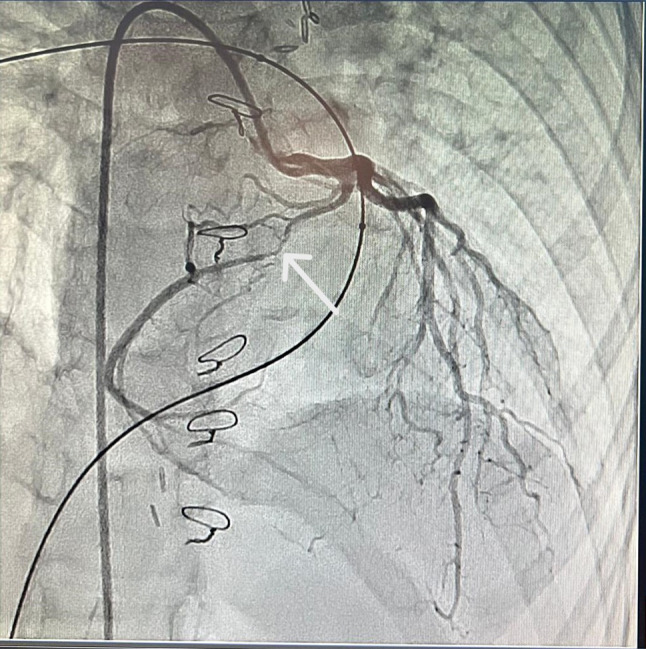

冠状动脉旁路移植术(CABG)在儿童心脏手术中是一种非常罕见的手术,主要是因为这一人群的冠状动脉疾病发病率低。然而,当有指示时,使用胸内动脉(ITA)作为移植物对于确保长期成功至关重要。本病例报告描述了一位冠状动脉异常的患者,右冠状动脉从左主冠状动脉出发,沿右心室流出道横贯。患者在Rastelli手术后出现晚期冠状动脉压迫,突出了ITA移植物在手术治疗中的关键作用。

Coronary artery bypass grafting (CABG) is an exceedingly rare procedure in pediatric cardiac surgery, primarily due to the low incidence of coronary artery disease in this population. However, when indicated, the use of the internal thoracic artery (ITA) as a graft is crucial for ensuring long-term success. This case report describes a patient with a coronary artery anomaly where the right coronary artery is taking its origin from the left main coronary artery and transversing along the right ventricle outflow tract. The patient experienced late coronary compression after Rastelli operation, highlighting the critical role of ITA grafts in the surgical treatment.